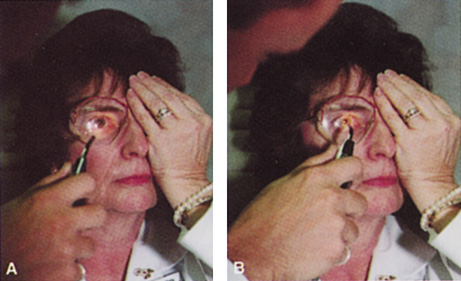

Many patients are most bothered by cataract-induced glare. For these patients, acuity testing under glare situations is indicated. There are several methods to assess visual acuity reduction by glare. The choice of method is often best dictated by the patient's history. If a patient complains of glare problems in the supermarket, or other uniformly illuminated environment, the brightness acuity test can be performed (Mentor Ophthalmics). For this test, the specially illuminated handpiece is held in front of the tested eye using best spectacle correction (Fig. 1). The Snellen acuity is rechecked and can be recorded on each of three light settings.

Patients who complain of glare from point sources of light, such as oncoming headlights or bright sunshine, may be best evaluated by a different form of glare testing. To simulate the environment of the patients' symptoms, Snellen acuity is measured while directing a point source of light obliquely toward the eye outside their best spectacle correction or outside of a phoropter dialed in with their best manifest refraction (Fig. 2).